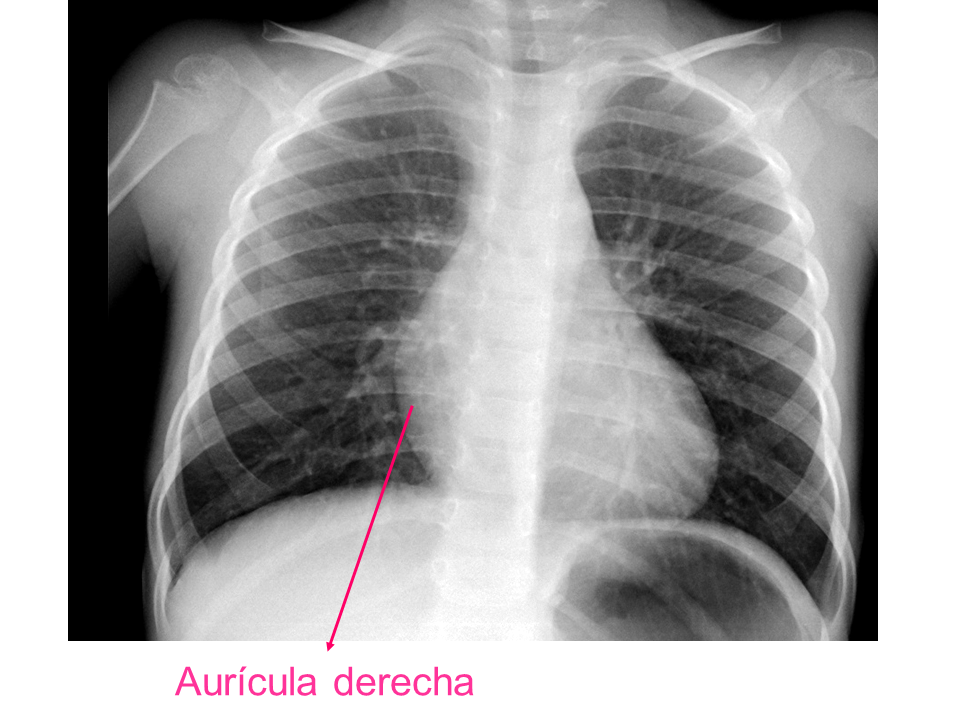

Para una adecuada lectura sistemática de la radiografía de tórax, debemos conocer la anatomía radiológica básica e identificar determinadas estructuras2.

• Aurícula derecha